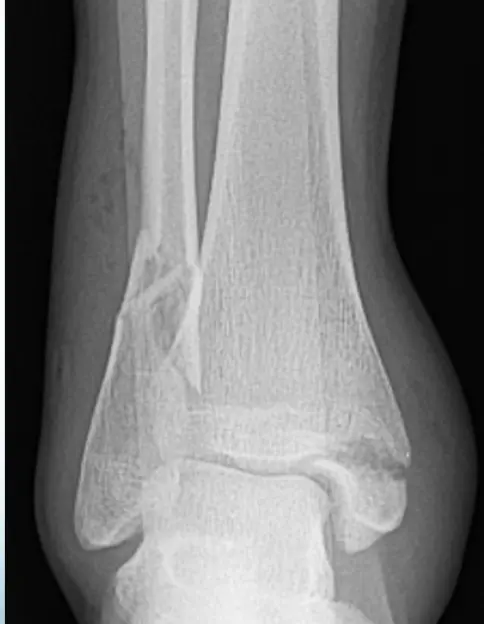

Important to have two views

Reading a fracture

- Site: Shaft tibia â lowerâŻ1/3

- Type: Simple

- Fracture line: Transverse

- Displacements: Lateral & posterior shift; minimal medial & anterior tilt

- Special issues: Joint above not visualized